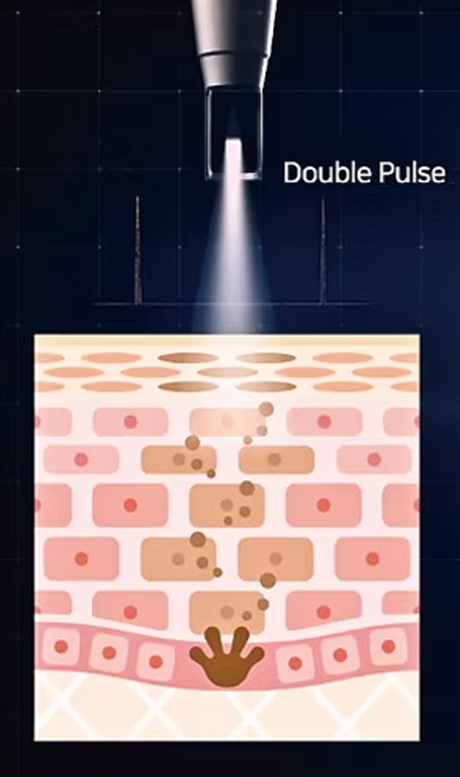

표피 손상없는

멀티펄스 레이저

최대출력 3,000mJ의 에너지에서 4~8개의 다중펄스를 발생시켜

강력하고 부드러운, 레이저 치료의 부작용을 최소화한 시술입니다.

LIOB(Laser Induced Optical Breakdown) 효과를 이용해

플라즈마를 발생시키고 이 효과로 손상된 조직을 회복시켜

매끄러운 피부로 거듭나게 합니다.